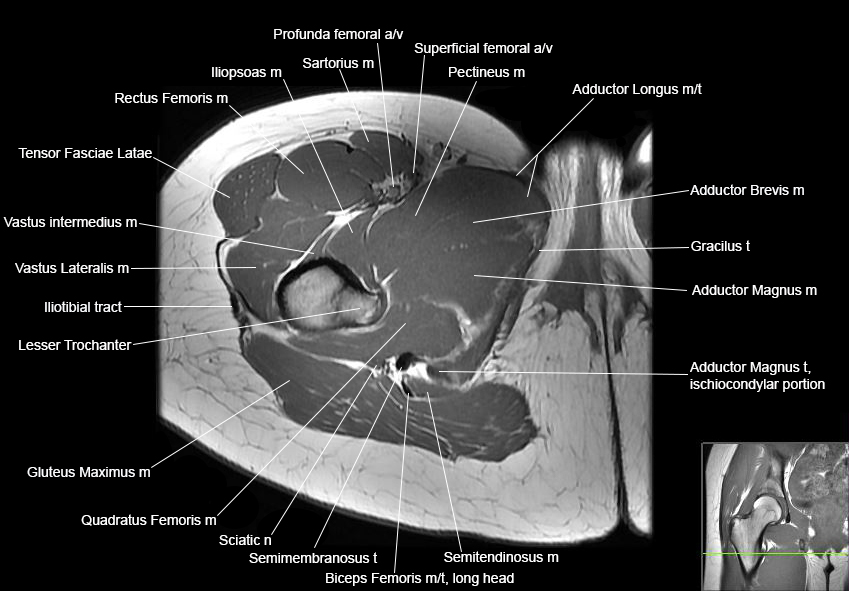

Hip

Basic Hip MRI

MRI Hip Anatomy

Scroll using the mouse wheel or the arrows